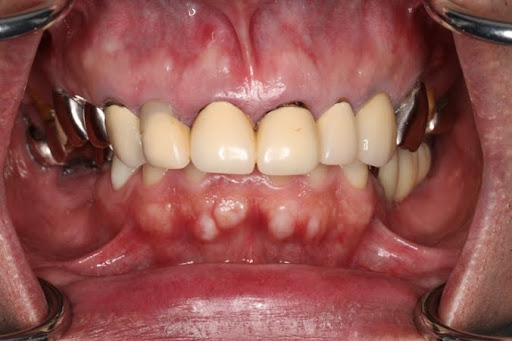

症例